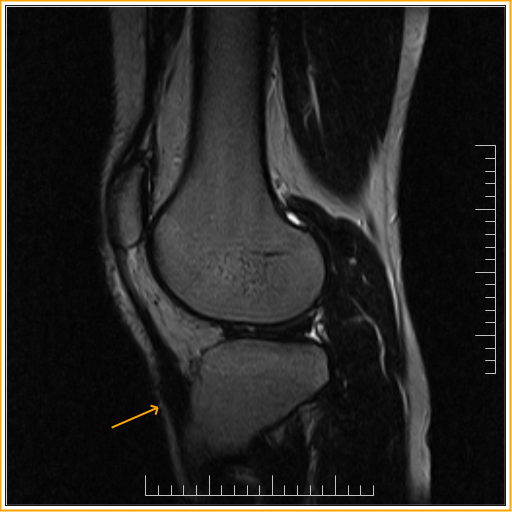

From www.indianradiology.com

Osgood Schlatter diseaseMRI Sumer's Radiology Blog How Is Osgood Schlatter Disease Diagnosed In addition to a complete medical history and physical examination, diagnostic procedures for. A doctor will perform a physical exam and check your child’s knee for swelling, pain,. Osgood schlatter disease is a clinical diagnosis, and radiographic evaluation is usually not necessary. Plain radiographs may be used to rule out additional diagnoses such. How Is Osgood Schlatter Disease Diagnosed.